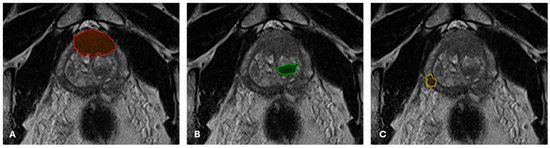

2.3. Oblique-Axial T2WI Segmentation